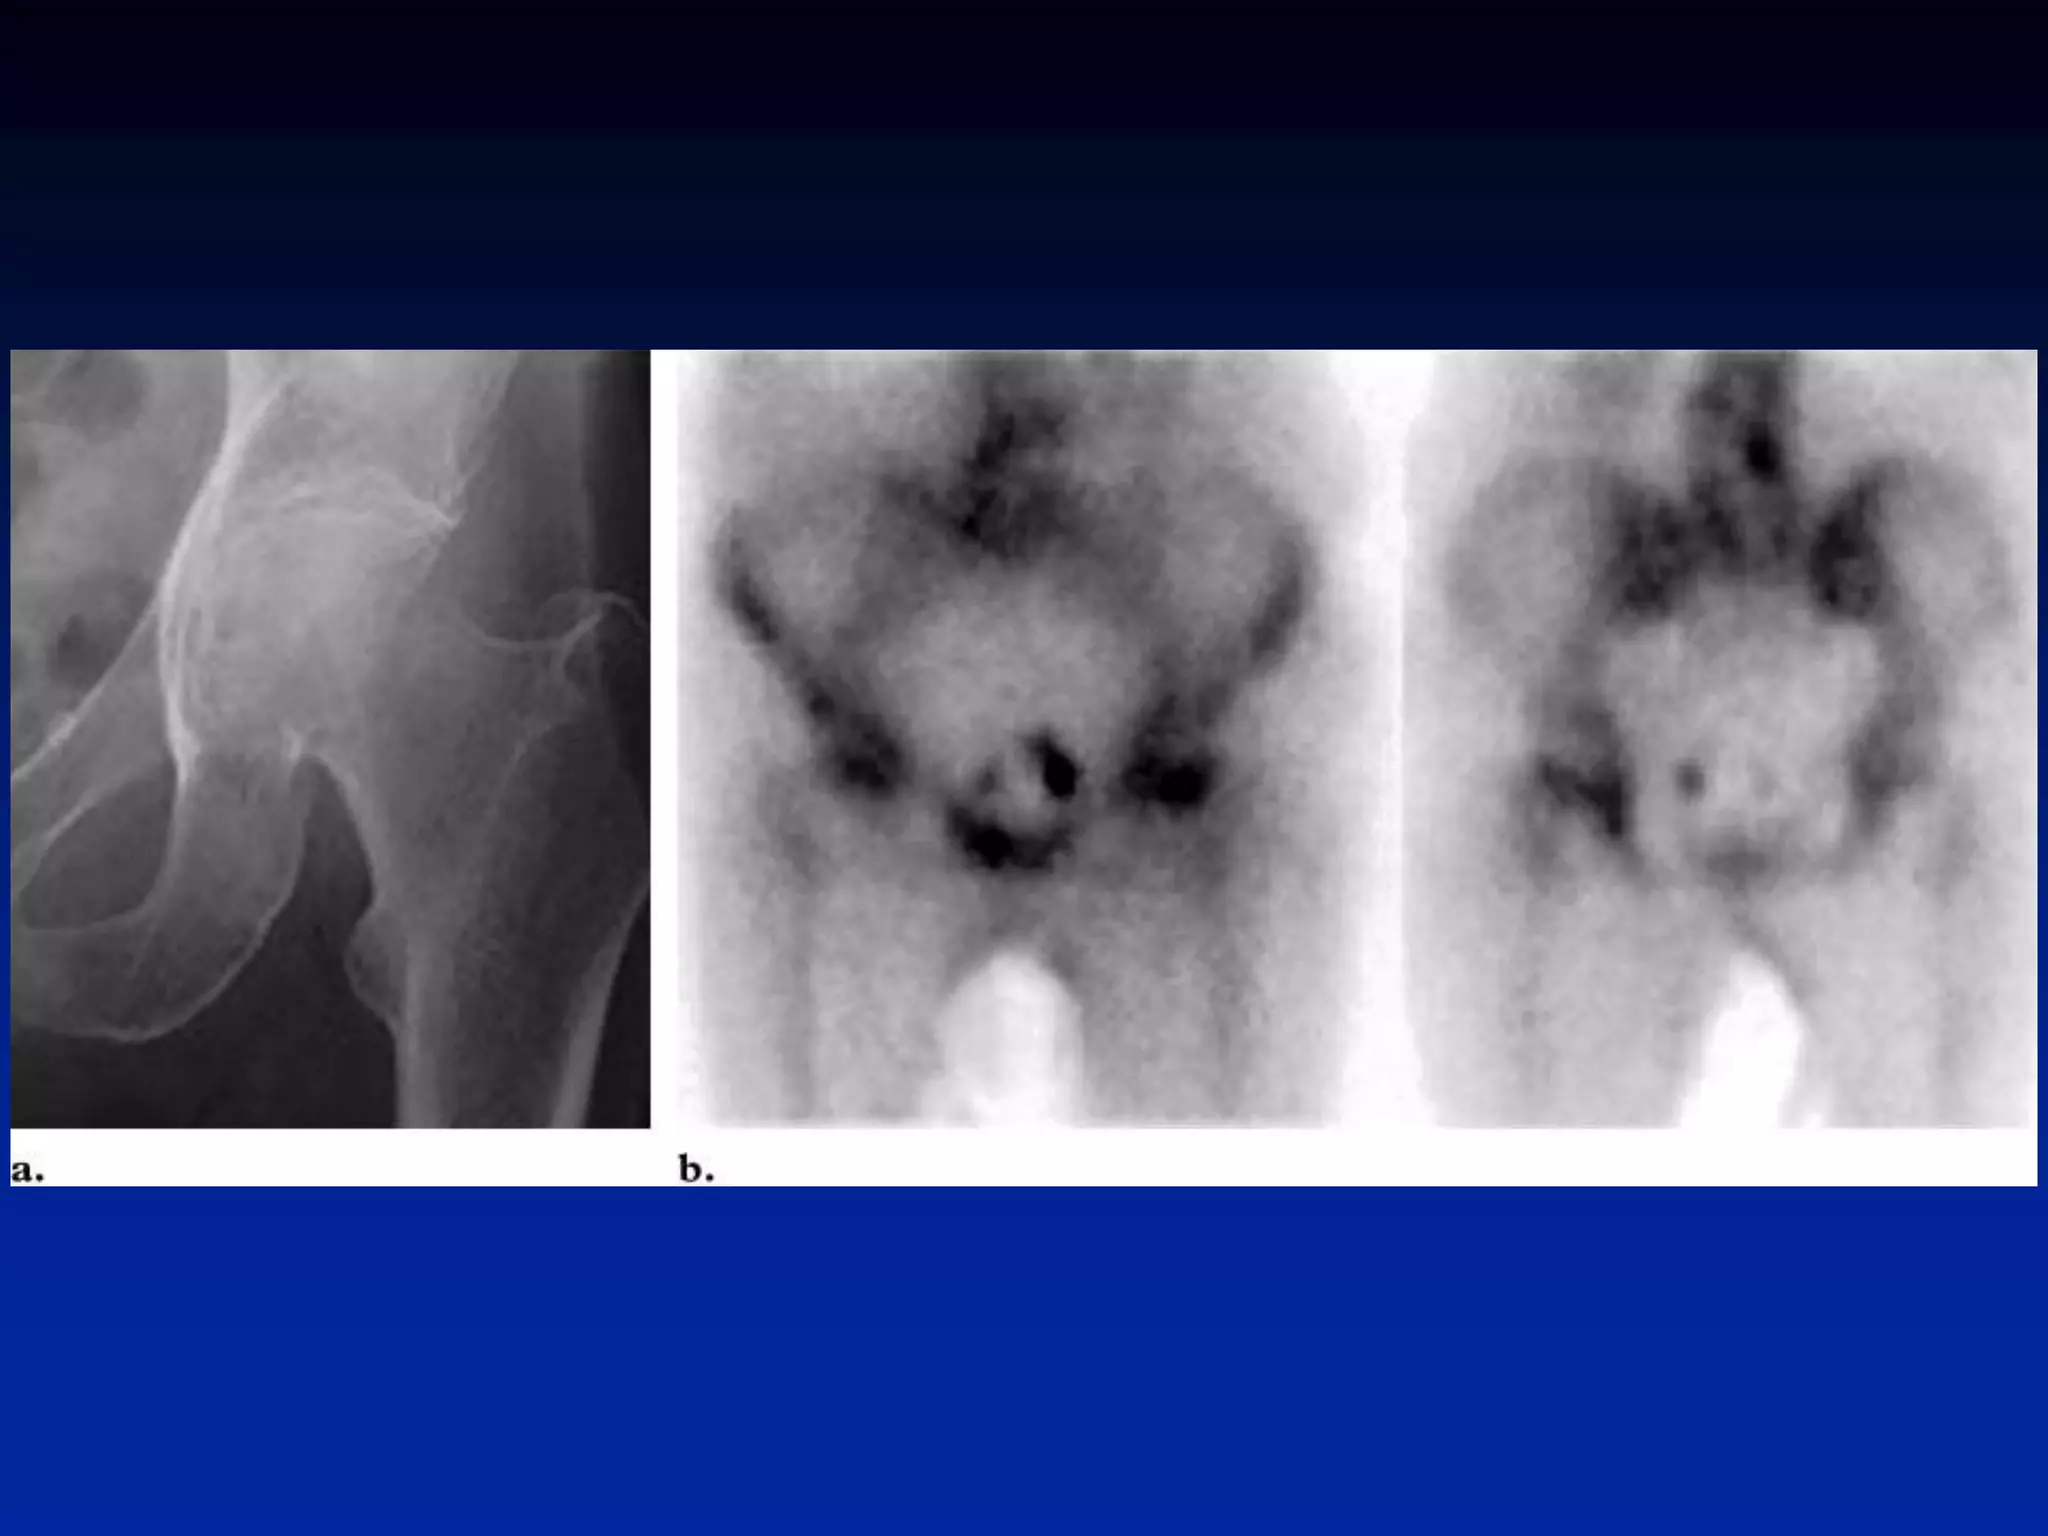

Prosthesis-Loosening vs

Infection

• increased uptake normal after surgery

–~1y w/ cemented, ~2-3y w/ non-cemented

• start w/ bone scan if negative no

infection or loosening

• if positive and unclear whether

loosening or infection consider Tc-

HMPAO-WBC scan to differentiate

Infection from loosening

l

loosening Infection

Prosthesis-Loosening vs Infection • increaseduptake normal after surgery –~1y w/ cemented, ~2-3y w/ non-cemented • start w/ bone scan if negative no infection or loosening • if positive and unclear whether loosening or infection consider Tc- HMPAO-WBC scan to differentiate Infection from loosening l